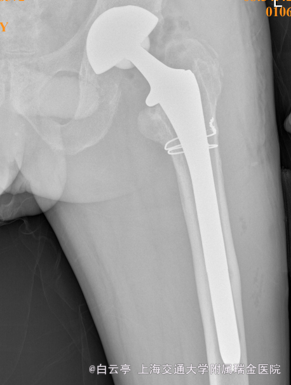

诊断:髋关节假体松动 治疗:左侧髋关节翻修术

随访:患者2周后手术切口月愈合好。6周后髋关节活动度好。 讨论:髋关节翻修的量随着初次THA大量增加而不断增加。当对翻修的了解程度深入后对初次THA也有很大的帮助。